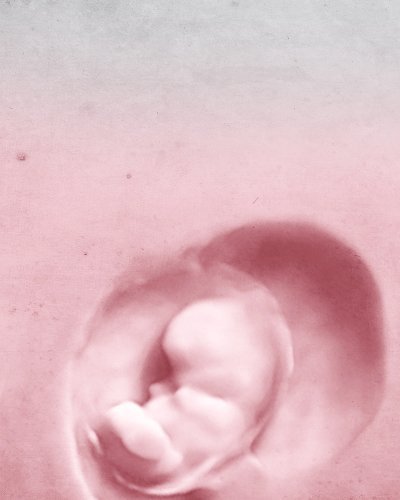

AANGEPASTE VRUCHTBAARHEIDSSTUDIE OM

DE BEHANDELING TE INDIVIDUALISEREN